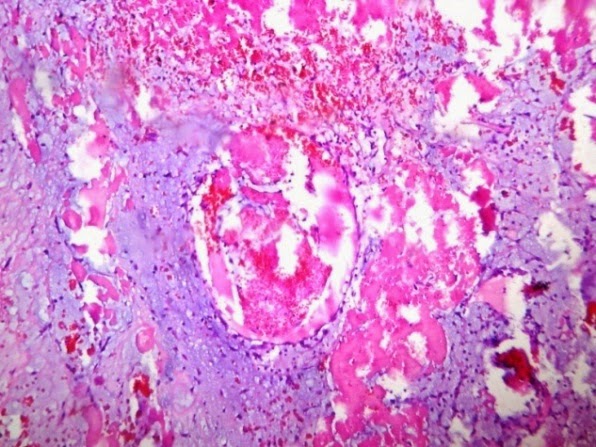

Гистологические особенности карциноида червеобразного отростка